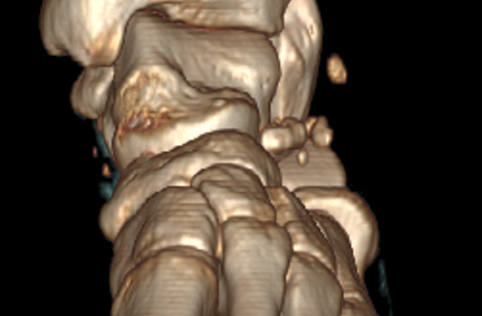

△术后横截面显示骨折复位良好